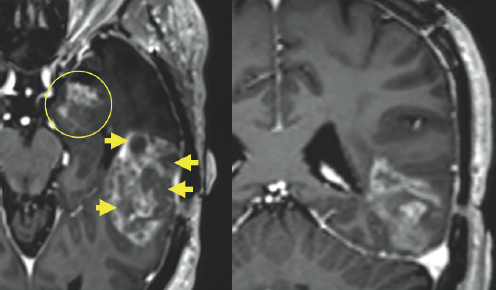

Variations of gray color are enclosed by a white outline. In the center of the image, there is a very small white blob highlighted by a red circle. In the top right of the image, there is a white colored blob highlighted by a yellow circle. (Right) Gray colored variations are enclosed by a black and white outline. To the right of the image, there is a significantly large white blob highlighted by a yellow oval.

FIGURE 2.2 Brain MRI before surgery. Additional nodular areas of abnormal enhancement that appear bright after being injected with IV contrast are noted in the anterior temporal lobe (yellow circle) and the left aspect of the midbrain (red circle). There is surrounding signal alteration on the MRI sequence image most consistent with swelling (yellow oval).